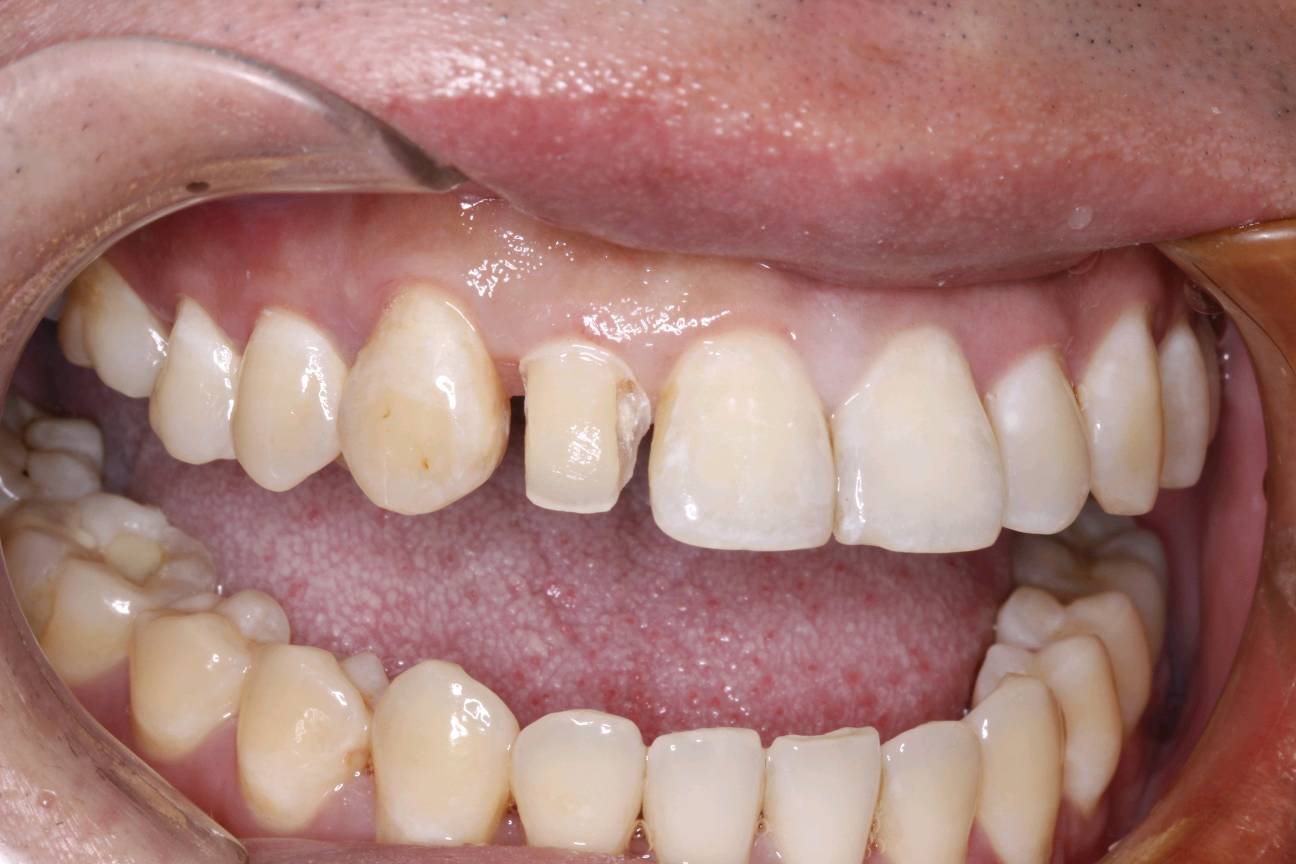

患者男三十岁,12近中邻面龋坏,经常性食物嵌塞,探+-,扣-,冷水入洞一过性敏感。牙面色泽偏黄,牙颈部呈白垩色。余无特殊。治疗计划:去腐+复合树脂充填+贴面修复。如果偶感食物嵌塞,还是要到口腔诊所及时就医检查。很有可能是发生龋坏,需要及时修复,如果出现疼痛的现象,就不能靠单纯的补牙修复那么简单了。所以每半年定期检查牙齿,才能避免出现严重的口腔疾病。通过西诺德口扫系统,3D打印口腔模型。当天上午备牙 下午即可佩戴。色泽形态自然,边缘密合,患者满意!

术后